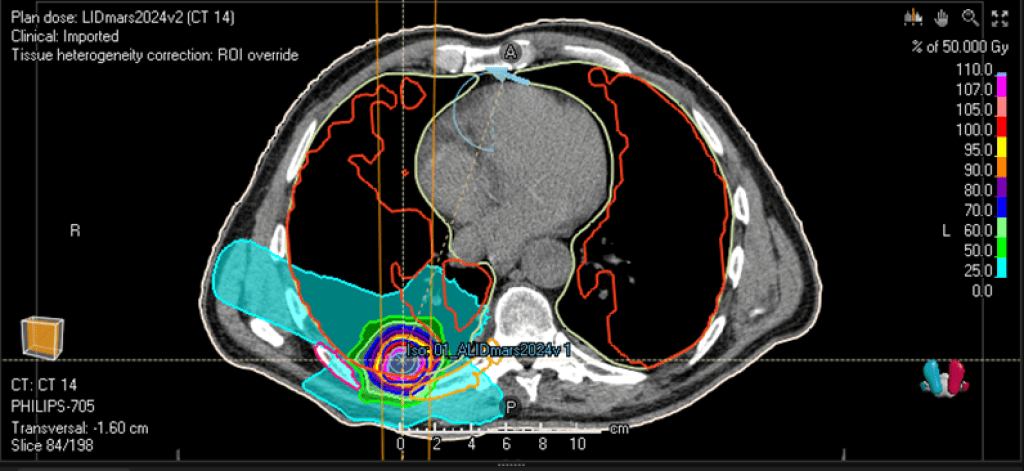

La formation explore également les innovations technologiques et physiques en radiothérapie, notamment l'utilisation de techniques avancées telles que la modulation spatiale de dose, les photons avancés (IMRT, VMAT, SBRT adaptative), l'imagerie en temps réel ou encore les approches émergentes comme le FLASH ou les nouvelles sources d'irradiation.

• des exemples cliniques et technologiques issus de la pratique en radiothérapie,